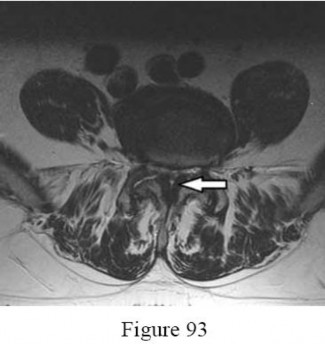

A 55-year-old male with known renal cell carcinoma presents with progressive lower extremity weakness and bowel dysfunction.

Imaging reveals a destructive metastatic lesion at L3 causing mechanical collapse and severe canal stenosis. Operative decompression and stabilization are planned. What is the most critical preoperative step?

Explanation